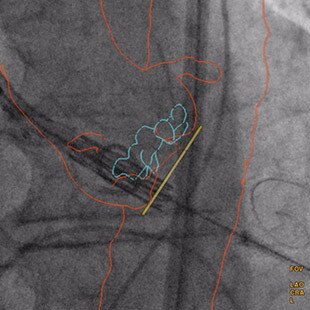

- Roy, et al. Novel Integrated 3D Multi-Detector Computed Tomography and Fluoroscopy Fusion for Left Atrial Appendage Occlusion Procedures. Catheter Cardiovasc Interv 2017;Mar 17, DOI:10.1002/ccd.26998